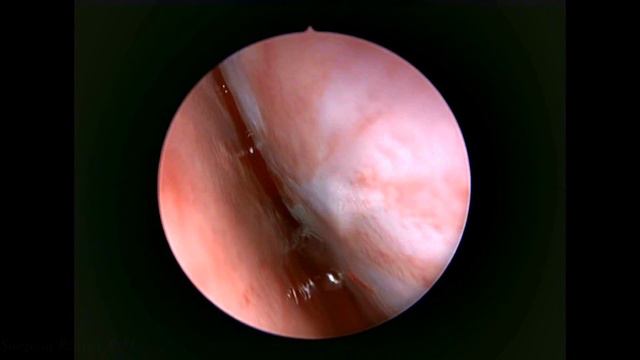

ЭНДОСКОПИЧЕСКАЯ СЕПТОПЛАСТИКА